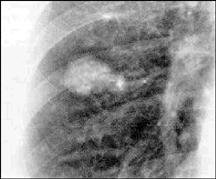

The presence of calcification within a nodule on plain film, tomography, or a CT is a reliable indicator that the nodule is benign. Classically, granulomas may show a laminated or a concentrically ringed calcification pattern. Other benign calcification patterns include central, diffuse, and "popcorn ball," which may be seen with hamartomas (Fig 2). About 10 percent of malignant lesions show evidence of calcification on plain chest film, and eccentric calcification should raise suspicion of malignancy.

|

| Fig. 2: Posteroanterior chest roentgenogram showing a 2 x 2.5 cm nodule with "popcorn ball" calcification, which is indicative of hamartoma. |

Great strides have been made in the identification of nodules as benign utilizing CT. Chest CT is more sensitive than plain film or tomography in the detection of calcium, and multiple nodules may be identified. The standard CT is more sensitive in identifying calcium as well as detecting hamartomas by the presence of fat.